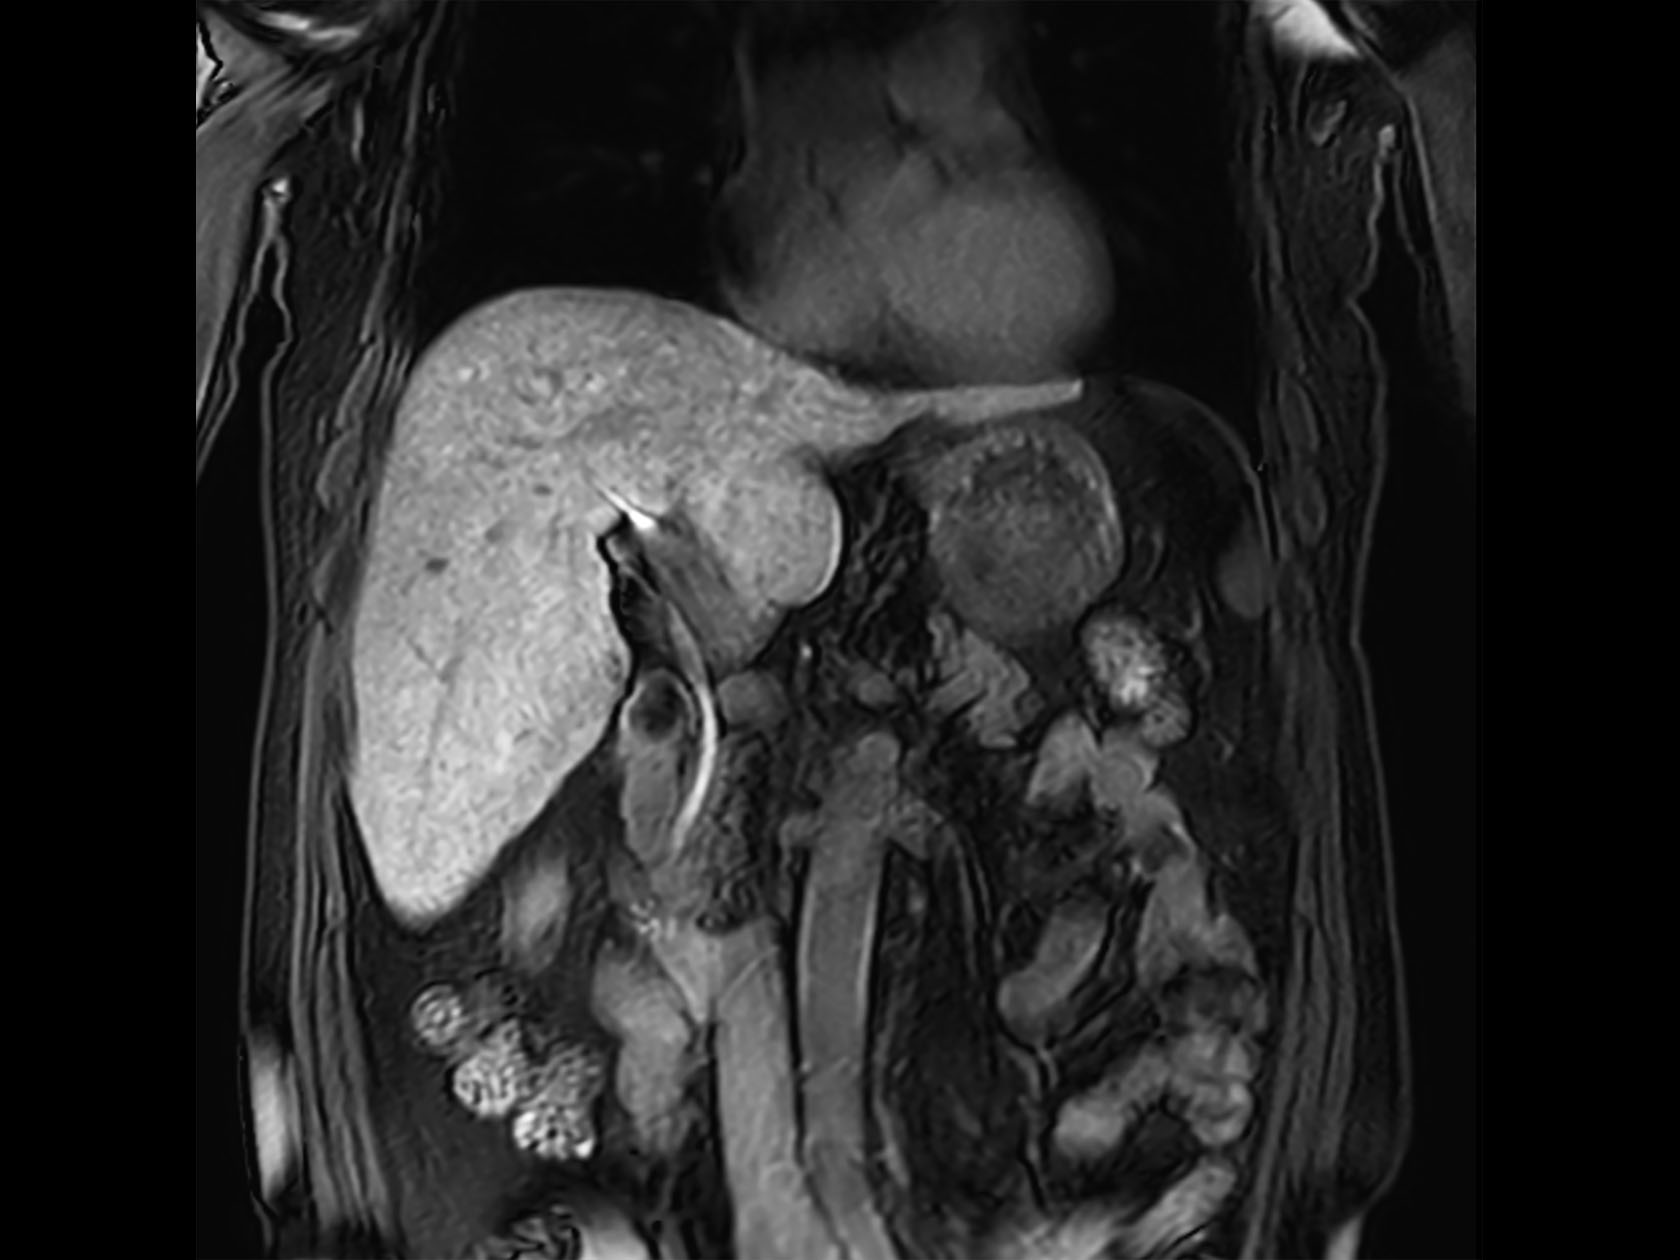

Coronal T2w TSE

Coronal eTHRIVE